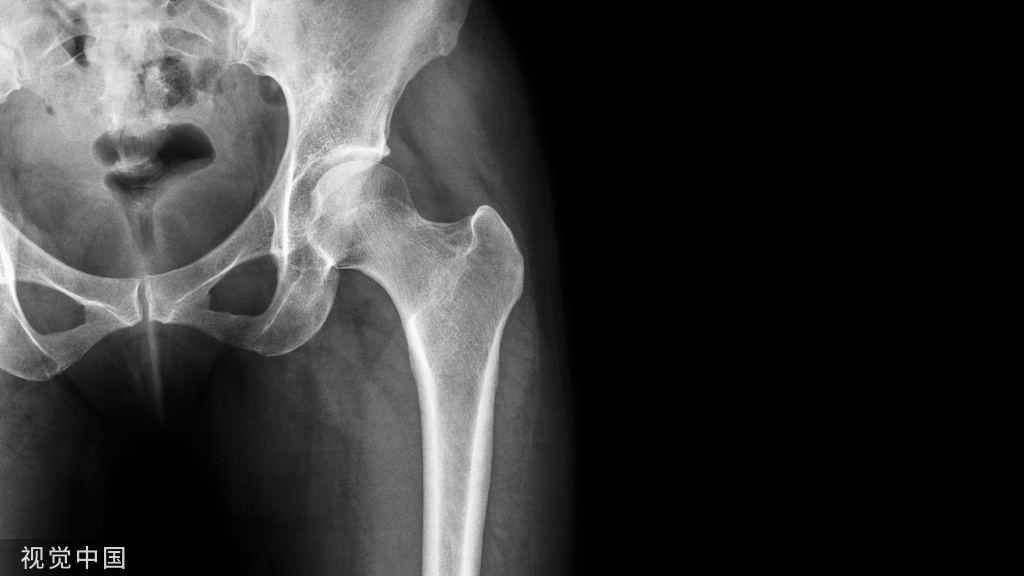

骨科大手术围手术期营养不良的发生率较高,但其中仅有极少数的患者得到及时的诊断与治疗。营养不良是骨科大手术患者术后并发症的独立危险因素。围手术期合理的营养支持可减少围手术期并发症、加速患者康复,是实现骨科加速康复的关键环节之一。为了进一步加强骨科大手术加速康复围手术期营养管理,提高医疗质量和安全,国家卫生健康委加速康复外科专家委员会骨科专家组、中国研究型医院学会骨科加速康复专业委员会、中国康复技术转化及促进会骨科加速康复专业委员会联合多学科专家成立骨科加速康复系列共识编写专家委员会,以临床问题为导向,遵循循证医学原则,归纳出4 个方面的问题:①围手术期营养不良的特征与营养支持目标;②术前营养风险筛查及营养状况评定;③术后营养风险筛查及营养状况评定;④围手术期营养支持。按照上述4 个方面的问题进行文献检索和归纳,经过反复讨论和修改后形成本共识,期望其为我国骨科加速康复围手术期营养管理的多学科协作起到积极的推动作用,最终达到加速患者康复的目的。

营养不良是指由于摄入不足或利用障碍引起能量或营养素缺乏的状态,进而导致人体组成改变、生理和精神功能下降,有可能导致不良临床结局[1]。围手术期营养不良多由于摄入不足、吸收障碍、过度损耗所造成[2-3]。随着我国人口老龄化进展的加快,骨科老年住院患者明显增多,其营养不良问题也越来越突出。据报道,23%~60%的老年住院患者存在营养不良[4-5],骨科创伤住院患者的营养不良率高达50%[6]。然而,研究显示仅有10%的营养不良患者得到诊断与治疗。营养不良是骨科大手术患者术后并发症的独立危险因素,其不仅损害患者的机体生理功能,而且增加切口并发症、术后感染、多器官衰竭和围手术期死亡的风险[7-10]。目前的证据表明,围手术期合理的营养支持能改善患者的临床疗效,减少围手术期并发症,加速患者康复[11-18]。